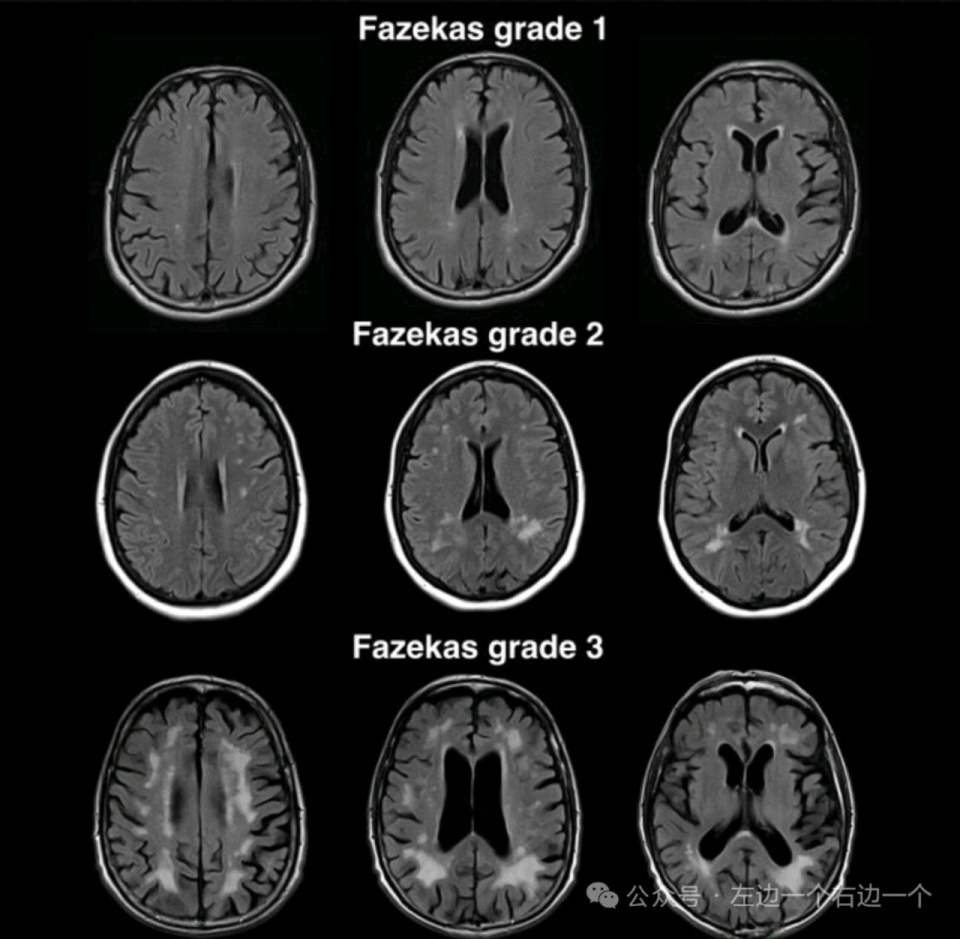

根据脑白质病变的影像学特征不同,通常用改良Fazekas分级来表示(图一图二)。

改良Fazekas法(3级):

Fazekas 1 级:斑点样;

Fazekas 2 级:斑块样(斑点部分融合);Fazekas 3 级:斑片样(病变大片融合)。